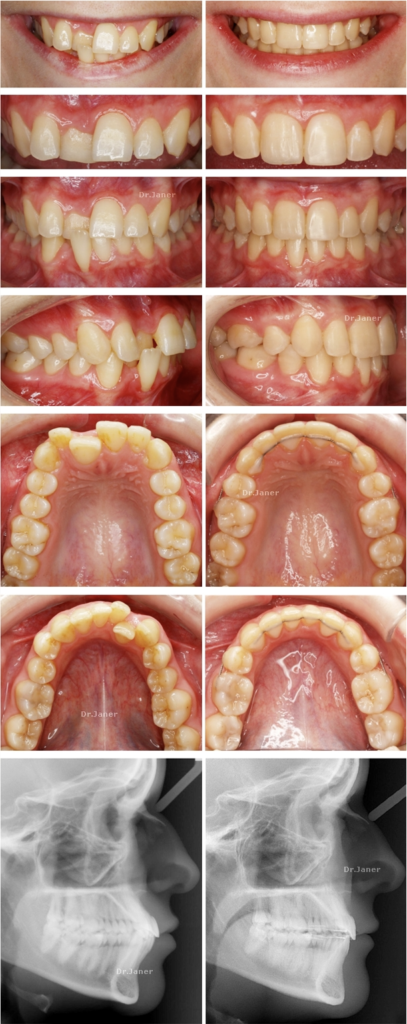

Paciente con 30 años y problemas de: dientes anteriores muy inclinados, mordida cruzada anterior y recesión gingival de un incisivo de la parte inferior.

Especialidades usadas: ortodoncia +/- periodoncia mucogingival -injerto de encía en incisivo inferior (41).

Resultados logrados en 26 meses de tratamiento: alineamiento dental, resolución de la mordida cruzada anterior, con extracciones dentales de cuatro premolares. (La recesión gingival mejora con la ortodoncia y se decide monitorizar la encía del incisivo)